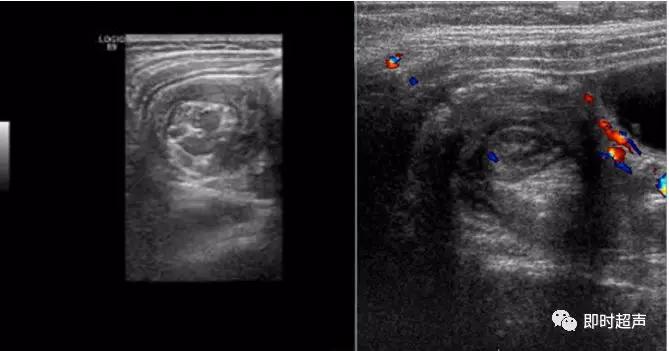

超声表现

低回声团:短轴 靶环征

长轴 套筒征

偏心 阑尾、息肉等

CDFI:局部血流信号增加

缺血坏死时血流信号消失

肠套叠超声表现

短轴切面同心圆征

长轴切面套筒征、短轴切面同心圆征